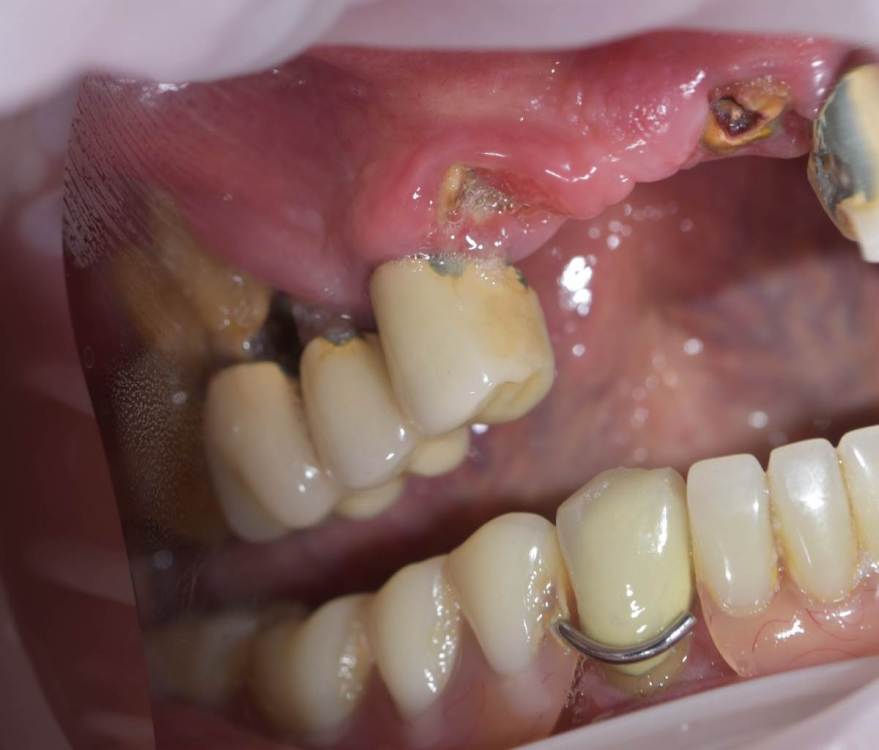

TIGER Опубликовано 13 июня, 2022 Поделиться Опубликовано 13 июня, 2022 (изменено) Всем привет!Довольно сложная исходная ситуация,пожелания пациента минимум вмешательств ,никаких костных пластик.В таких случаях я предпочитаю съёмные конструкции на балочной фиксации из-за возможности гигиены,ибо у так пациентов всё печально с этим.После обсуждения с пациентом он одобрил план действий и будущую конструкцию .Произведено изготовление шаблона,по навигации установлены импланты 4 верх и 4 низ,временные несъёмные конструкции на мультиюнитах,через полгода 2 протеза на балочной фиксации? Изменено 13 июня, 2022 пользователем TIGER 6 1 Ссылка на комментарий

TIGER Опубликовано 13 июня, 2022 Автор Поделиться Опубликовано 13 июня, 2022 Ситуация до Ссылка на комментарий